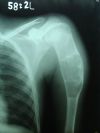

Aneurysmal bone cyst left proximal humerus in a 14 yr old